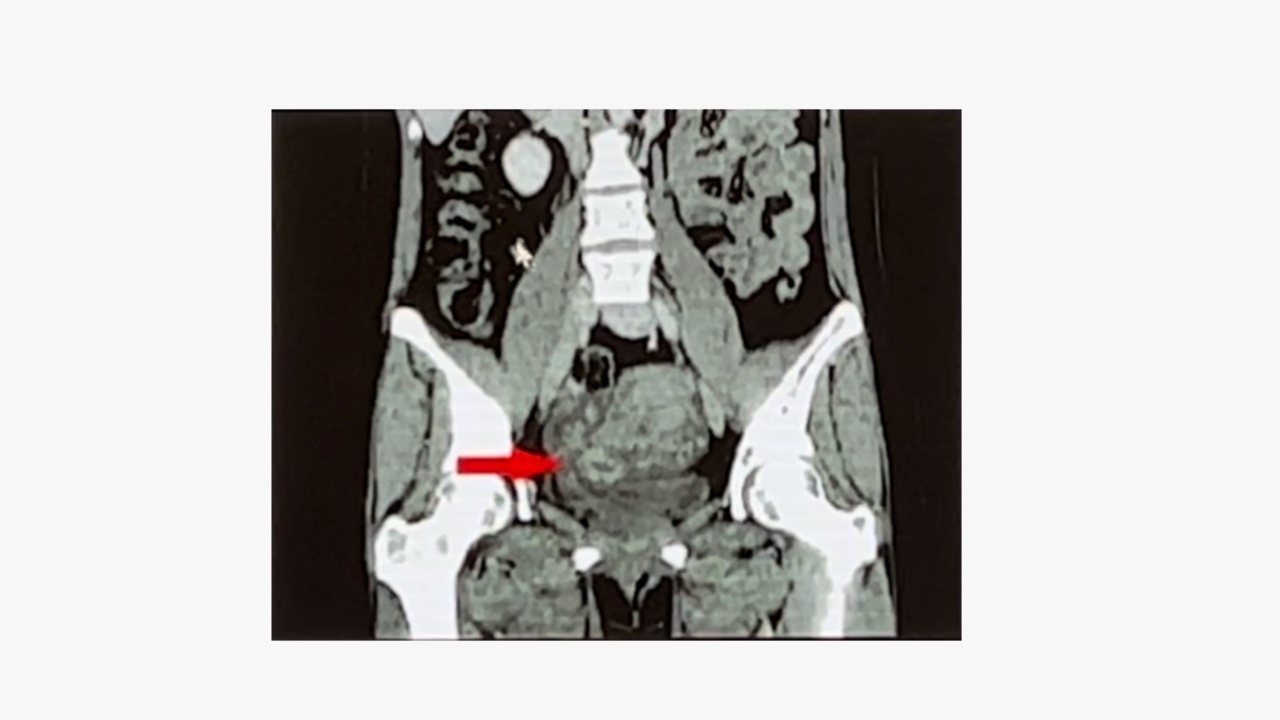

3、CT检查

盆腔CT:显示子宫右侧有造影剂强化的结节,盆腔肿物由于血管丰富呈明显不规则强化,可推挤膀胱向右前方移位。

CTA:显示静脉内平滑肌瘤起源于左侧宫旁,沿着左侧髂内静脉、髂总静脉、下腔静脉一直延伸到右心房。